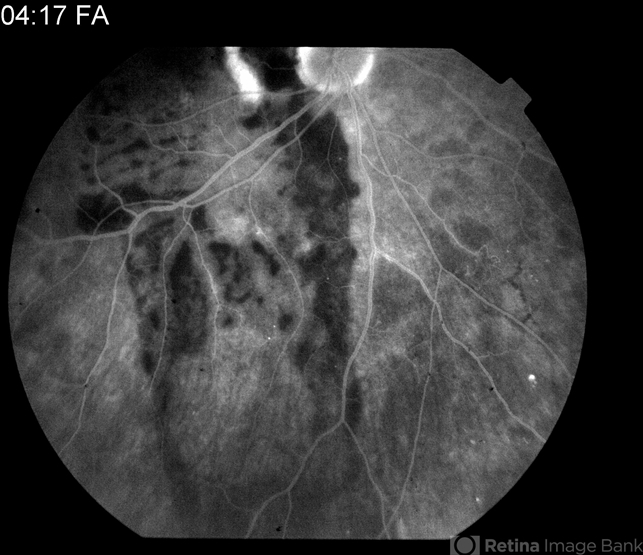

By Raj K. Maturi, MD

Midwest Eye Institute & Retina Partners Midwest - Uploaded on Sep 7, 2012.

- subretinal hemorrhage

- Char Harris, Midwest Eye Institute

Fundus camera

TRC 50ex